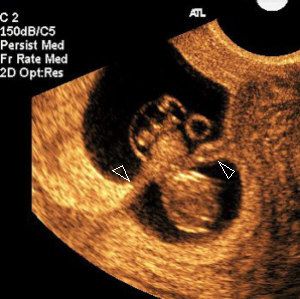

Amniotic band syndrome is very rare and has poor outcomes. Obstetric ultrasound can identify potential anatomic abnormalities.